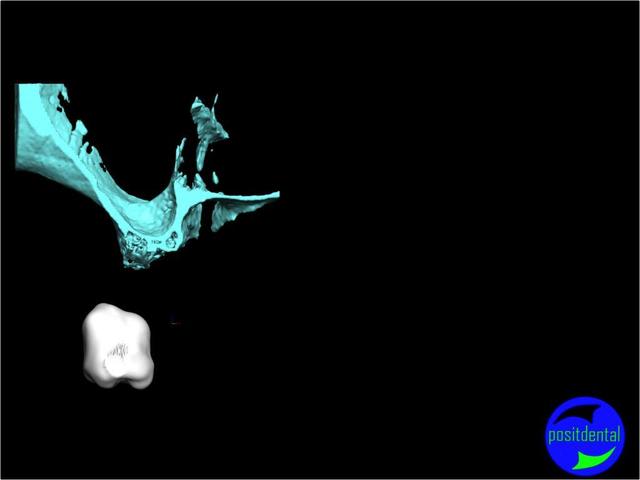

une autre vue du photshopman:

modèle stéréo du à la gentillesse de Posit